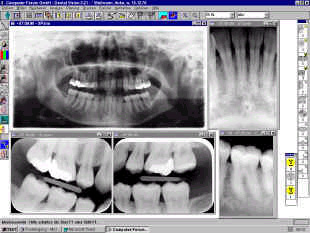

Système SIDEXIS : Rx numérique.

Les images dentaires sont visualisables instantanément à l'écran.

Rx numérique